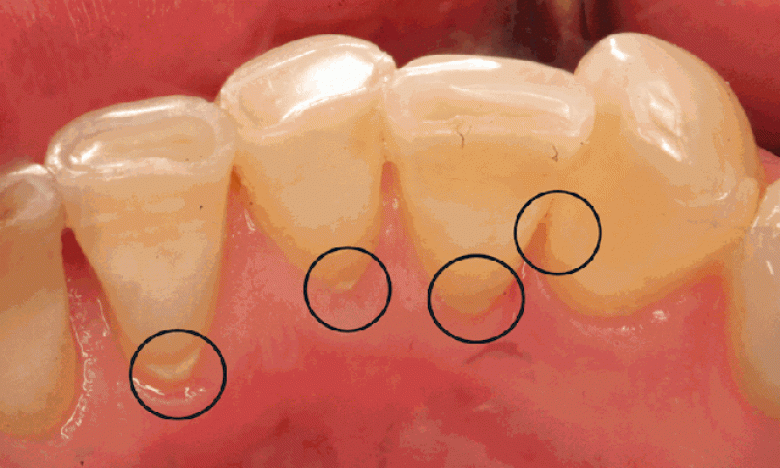

Ազատվեք կարիեսից՝ ընդամենը մեկ բաղադրիչի օգնությամբ

Այս մեկ բաղադրիչը, որը հնարավոր է նաև հենց այս պահին ունեք տանը, կօգնի կանխել կամ վերացնել կարիեսը:

Եթե չունեք, ապա այս նյութը կարդալուց հետո անպայման կցանկանաք գնել այն:

Կոկոսի յուղը լավագույն ձևով պայքարում է կարիեսի դեմ:

Պետք է ընդամենը 2 ճաշի գդալ կոկոսի յուղը լցնել բերանը և պահել 5 րոպե ու դատարկել բերանից:

Առաջին անգամ հնարավոր է անհարմարություններ զգաք, սակայն արժե այն կրկին կատարել:

Այս միջոցով կվերացնեք կարիեսը, գինգիվիտը, վատ շնչառությունը, էկզեման, ակնեն և մի շարք այլ հիվանդություններ:

Կոկոսի յուղը կարողանում է բերանի խոռոչից դուրս բերել բակտերիան: